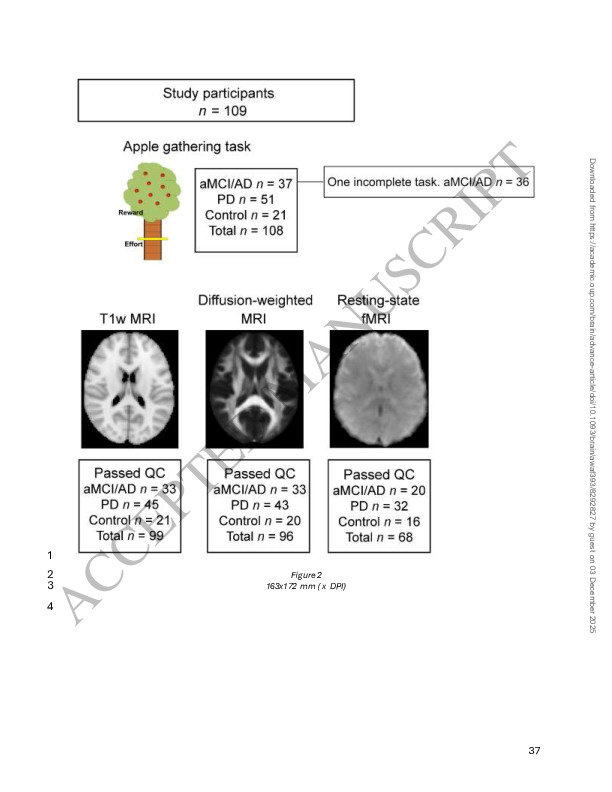

(2025). A transdiagnostic, multi-modal approach to understanding apathy: Methodological and analytical framework. NeuroImage: Reports, 5(4), 100289. 10.1016/j.ynirp.2025.100289

(2025). Apathy, effort-based decisions and brain integrity in Alzheimer’s and Parkinson’s diseases. Brain, p.awaf393.. 10.1093/brain/awaf393

(2024). Effort‐based decision making and white matter tracts associated with dimensions of apathy in Alzheimer’s and Parkinson’s disease. Alzheimer's & Dementia, 20, e095204.. 10.1002/alz.095204